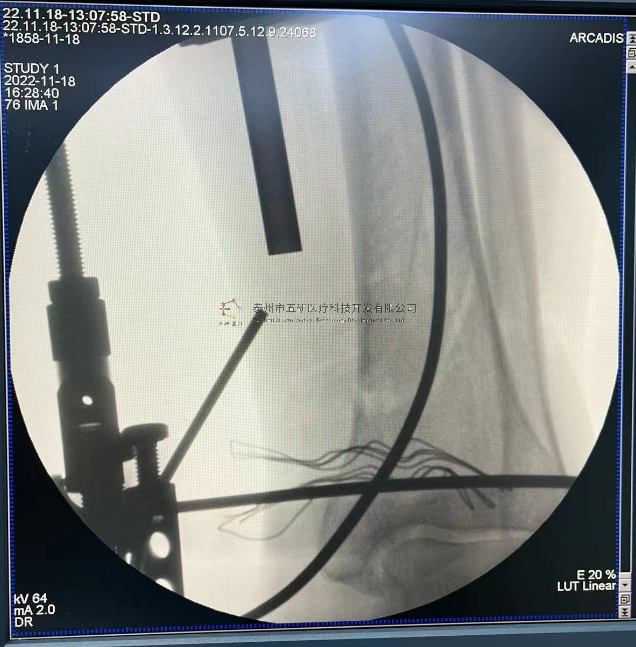

采用常規(guī)方法固定,自掌骨尺側(cè),約基底稍偏遠(yuǎn)處穿入螺紋針。